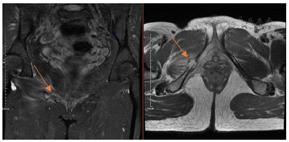

体格检查:体温36.5℃,心率90次/min,呼吸18次/min,血压130/90 mmHg(1 mmHg=0.133 kPa),心肺腹查体未见异常。专科检查:右髋部皮肤完好无破溃,无畸形及肿胀,肌肉无萎缩,骨盆无倾斜,双下肢基本等长;右侧腹股沟中点处压痛(+),叩痛(+),未触及肿块,髋关节周围轻度叩痛,下肢纵向叩击痛(±),右下肢皮温血运良好,足背动脉及胫后动脉搏动可触及;右髋关节屈曲、外展、外旋活动略受限,肌力Ⅳ级,膝关节、踝关节活动正常;右下肢直腿抬高试验及加强试验、大腿滚动试验、"4"字试验均阴性。血液化验结果无异常;骨盆CT重建结果示:右侧耻骨下支溶骨性骨质破坏,轻度膨胀,边缘清晰,未见骨膜反应(图1);髋部增强MRI结果示:右侧耻骨下支病变,考虑恶性肿瘤可能性大,骨转移瘤不除外(图2);全腹部CT、颅脑CT、肺部CT、胸腰椎MRI结果无异常;ECT示:右侧耻骨下支核素浓聚,考虑恶性肿瘤可能性大;胃肠镜结果回报:慢性非萎缩性胃炎。CT引导下病灶穿刺活检病理结果回报:送检物为纤维及骨组织,伴片状坏死,局部区域可见少量组织细胞样细胞、小淋巴细胞及少许嗜酸性粒细胞,结合免疫组化染色及影像学报告,考虑LCH。免疫组化结果:AE1/AE3(−),CD163(+),CD1a(+),Langerin(+),S-100(+),CD30(−)(图3)。

根治性肿瘤切除术。术中见:肿瘤呈淡红色鱼肉状,与周围组织结构分界不清,周围组织水肿,骨膜增厚,骨质破坏明显伴有病理性骨折(图4)。完整切除肿瘤及边缘1 cm正常骨质,切除的肿瘤送术后病理。术后病理结果示:送检物为纤维、骨及横纹肌组织,局部区域可见少量组织细胞小片灶状增生、组织细胞间及周围可见较多淋巴细胞、浆细胞及少许多核巨细胞,部分组织细胞核形不规则,可见核沟,结合免疫组化染色结果及病理切片结果,考虑朗格汉斯细胞组织细胞增生。免疫组化:AE1/AE3(−),CD163(+),S-100(+),CD1a(+),Langerin(+),CyclinD1(+),CD30(−),CD138(−),Kappa(−),Lambda(−),IgG(−),IgG4(−)(图5)。